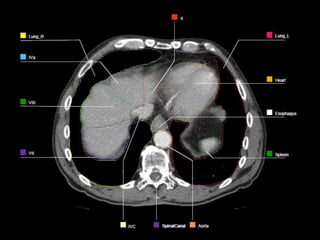

OARs  Liver  Kidney Stomach  Spinal Cord  Heart  Duodenum  Small Bowel  Lungs